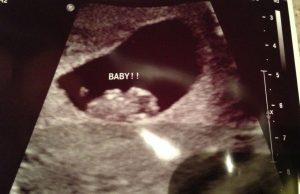

I de tidlige stadiene forblir babyen svært nær morkaken. Det viktigste er å se etter det lyse området.

Søk etter bildene fra din første ultralyd og ta følgende tips i betraktning:

- I tilfelle du finner din første vaginale ultralyd; Hvis fosteret er implantert til venstre, er det en jente. I tilfelle fosteret er funnet til høyre så blir det en gutt.

- Hvis du finner en abdominal ultralyd, bør resultatene leses som et speil. Derfor, hvis du ser at placenta er til høyre (det betyr at den faktisk er til venstre), bør du forvente en liten jente. Hvis du finner placenta til venstre (det betyr at det er til høyre) er det på tide å forberede seg på den lille gutten din.

Hvis du finner det vanskelig å tolke ultralydbildet eller å finne morkaken, ikke bekymre deg, bare spør legen din.